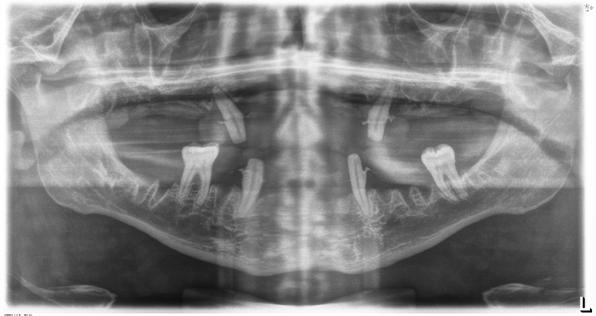

En la radiografía panorámica se observaron 28 dientes permanentes erupcionados y los gérmenes de los terceros molares, la longitud radicular es de 2:1; los senos, cóndilos y ramas mandibulares son simétricas, no presenta patologías (Figura 3).

Figura 3. Radiografía panorámica inicial.

Figura 3. Radiografía panorámica del paciente donde observamos la pérdida ósea ocasionada por la periodontitis agresiva y los dientes que se encuentran con el único sostén de los tejidos gingivales como los del frente anterior. Además, vemos cómo los molares de ambos cuadrantes superiores deben ser extraídos por presentar un mal pronóstico desde el punto de vista periodontal y restaurador.